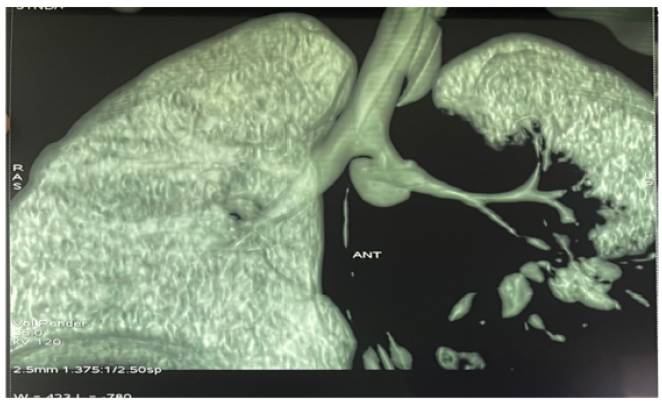

Severe Diabetic Ketoacidosis with an Acute Mediastinitis Complicating a Fungal Bronchopneumonia: A Pediatric Case

Salma Bellaftouh, Anas Erragh, Amine Afif, Karima Amenzoui, Kaoutar ElFakhr, Ouissal Aissaoui, Samira Kalouch and Abdelaziz Chlilek. 12(5): 61-66.